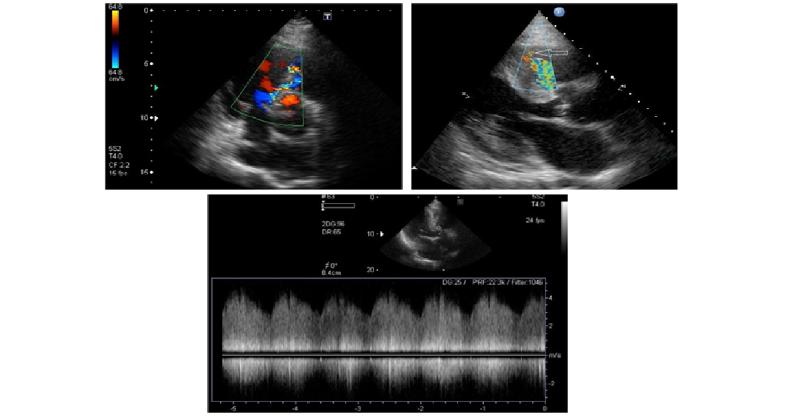

A Patient with Heart Failure Symptoms and Continuous Murmur

A 65-year-old man was admitted to the hospital having dyspnea, fatigue, and edema of both legs. Heart failure symptoms worsened during the last couple of weeks. He had long-standing arterial hypertension with poor control of arterial pressure without symptoms of coronary artery disease. An electrocardiogram showed sinus rhythm and left bundle branc